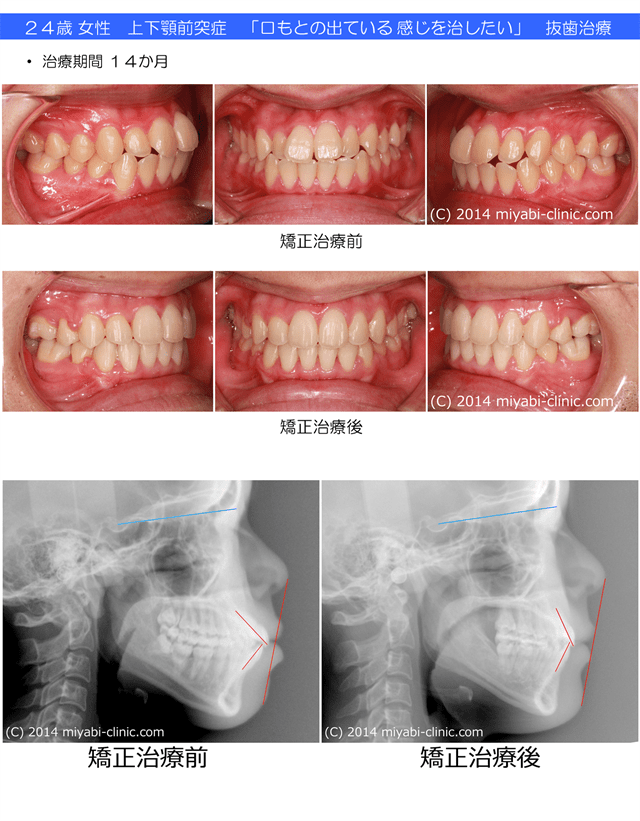

上下顎前突症とは上顎の前歯と、下顎の前歯の両方が傾斜して前に出ている状態を言います。

わかり易く言うと「上も”出っ歯”、下も”出っ歯”」ということになります。

上下の前歯の距離がないために、「”出っ歯”です」と指摘されることも少なく、”隠れ出っ歯”とも言えます。

口もとが ”もっさり”している

口が閉じにくい、または閉じきれない(油断すると前歯が出ている)

口を閉じると顎に梅干しのようなしわがよってしまう

唇がとがってしまうため、他人から不機嫌そうに見られてしまう

口紅が いつも歯についてしまう

など 口元が出ていて気になることが特徴です。

歯ならびだけでなく 口もとや、下顔面の変化を視野に入れた矯正治療がもとめられます。

治療前後で口もとの変化、下顔面の変化が大きく、お顔の印象がスッキリとして見えることが多いです。

34歳 女性 叢生を伴う 上下顎前突症 治療期間17か月 唇側矯正装置(ホワイトワイヤー)を使用した上下顎第一小臼歯抜歯治療 参考治療費 約65万円 (精密検査から終了まで) 矯正治療に伴う副作用の歯肉退縮、知覚過敏、失活、歯根吸収などは認められませんでした。